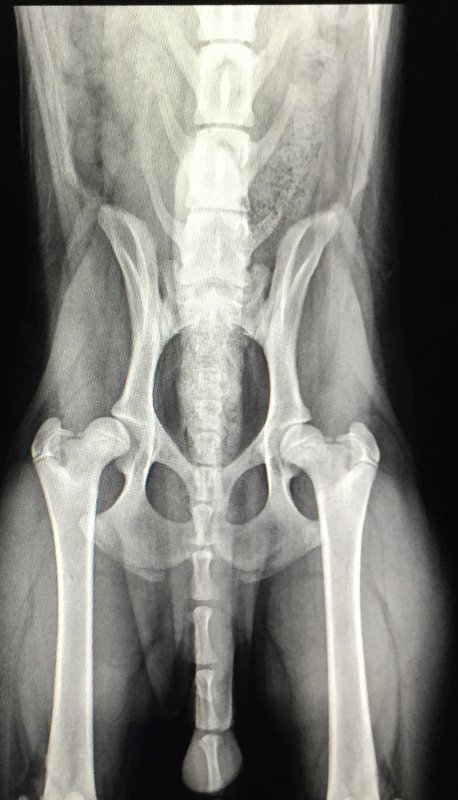

6 month Samoyed male X rays came back showing that right hip joint is "subluxated". *look at the space between the ball in the one hip* (left on your screen)

The X-ray is clear but the right femur was not positioned correctly. It was turned out a fraction therefore it is not really possible to see how far out the femur head is from the acetabulum [socket], although the socket does appear to be slightly shallow.

Looking at that X-ray again, I see more faults - which might or might not be the X-ray itself, due to incorrect positioning of the dog.

1 - The large spinal vertibrae above the pelvic bone are not in a straight line, therefore the dog was not held in the correct position.

2 - The right femur [on the left as it is shown] appears slightly thinner than the other one, again it could be because of an incorrect angle.

3 - Look at the tips of the base of the pelvic bone - the one on the right [again on the left as it is shown] shows through the femur, as if the femur is not yet calcified, ie is not solid.

So - either there is something wrong with the X-ray - and I have enlarged it and keep going back to look at it again, or there is something wrong with the femur itself. I am extremely surprised that the vet did not notice these things because the more I look at that X-ray the more obvious they are.

As I said, if that were my dog I would not just accept one X-ray, and I definitely would not accept that one, OR the fact that the vet did not notice them.